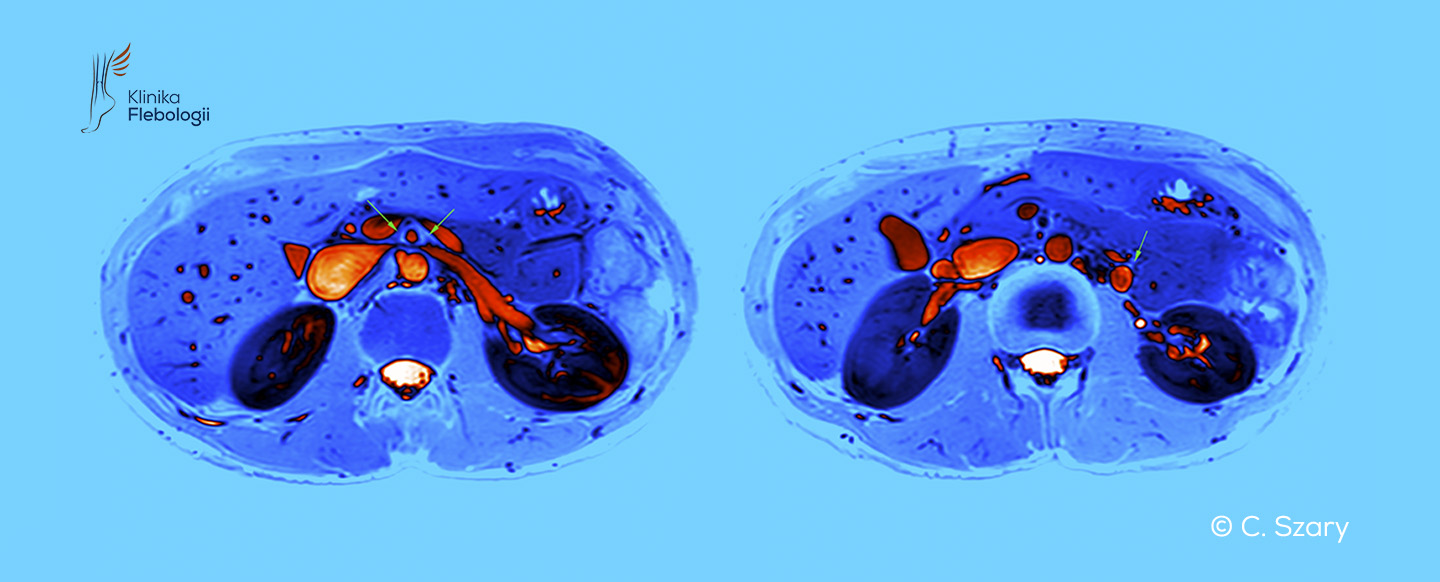

Zespół dziadka do orzechów związany jest ze zjawiskiem zaburzonego odpływu krwi żylnej z obszaru spływu lewej żyły nerkowej. Do ucisku lewej żyły nerkowej dochodzi najczęściej w miejscu jej krzyżowania na poziomie tętnicy krezkowej górnej (wariant przedni) lub w przypadku jej zaortalnego położenia (wariant tylny).

Zjawisko dziadka do orzechów należy do najczęstszych pierwotnych wariantów uciskowych na spływy żylne w organizmie człowieka. Najczęściej obserwujemy je na poziomie skrzyżowania lewej żyły nerkowej i tętnicy krezkowej górnej tuż pod jej odejściem od aorty brzusznej.

Anatomiczne zjawisko "dziadka do orzechów" polega na zaburzeniach odpływu krwi żylnej na poziomie spływu lewej żyły nerkowej. Związane jest ono z szeregiem objawów klinicznych, które wynikają z zaburzeń przepływu krwi w samej żyle nerkowej oraż żyłach do niej uchodzących, takich jak: żyły jajnikowa (lub jądrowa) czy żyły przykręgosłupowe.

Zespół dziadka do orzechów typowo powstaje w sytuacji, gdy tętnica krezkowa górna pod bardzo małym kątem odchodzi od aorty brzusznej, tylko nieznacznie się odchylając i wyginając. Sytuację pogłębia zazwyczaj uwydatniona lordoza lędźwiowa.